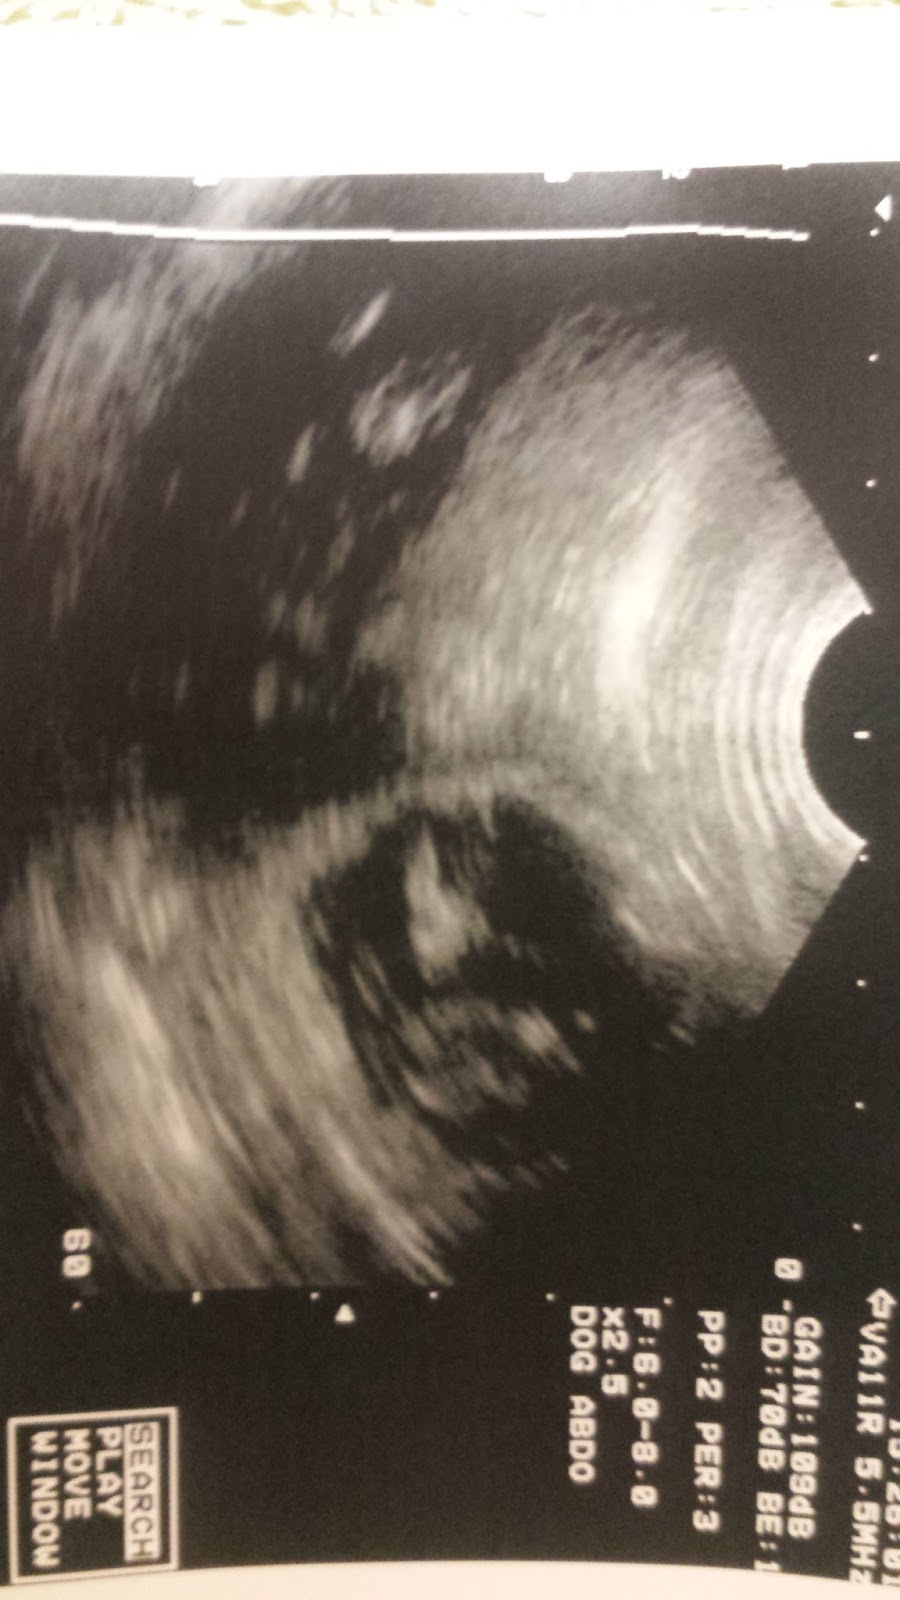

Puppies coming! !

We will be having puppies this fall at Lucas Legend Dalmatians

Zen- Blackthorn & PatchMt's ZEN at Lucas Legend and Luan Arberdeen's Let's make a deal.

Puppies due to arrive October 15 2015

Both parents have there Chic number and are LUA